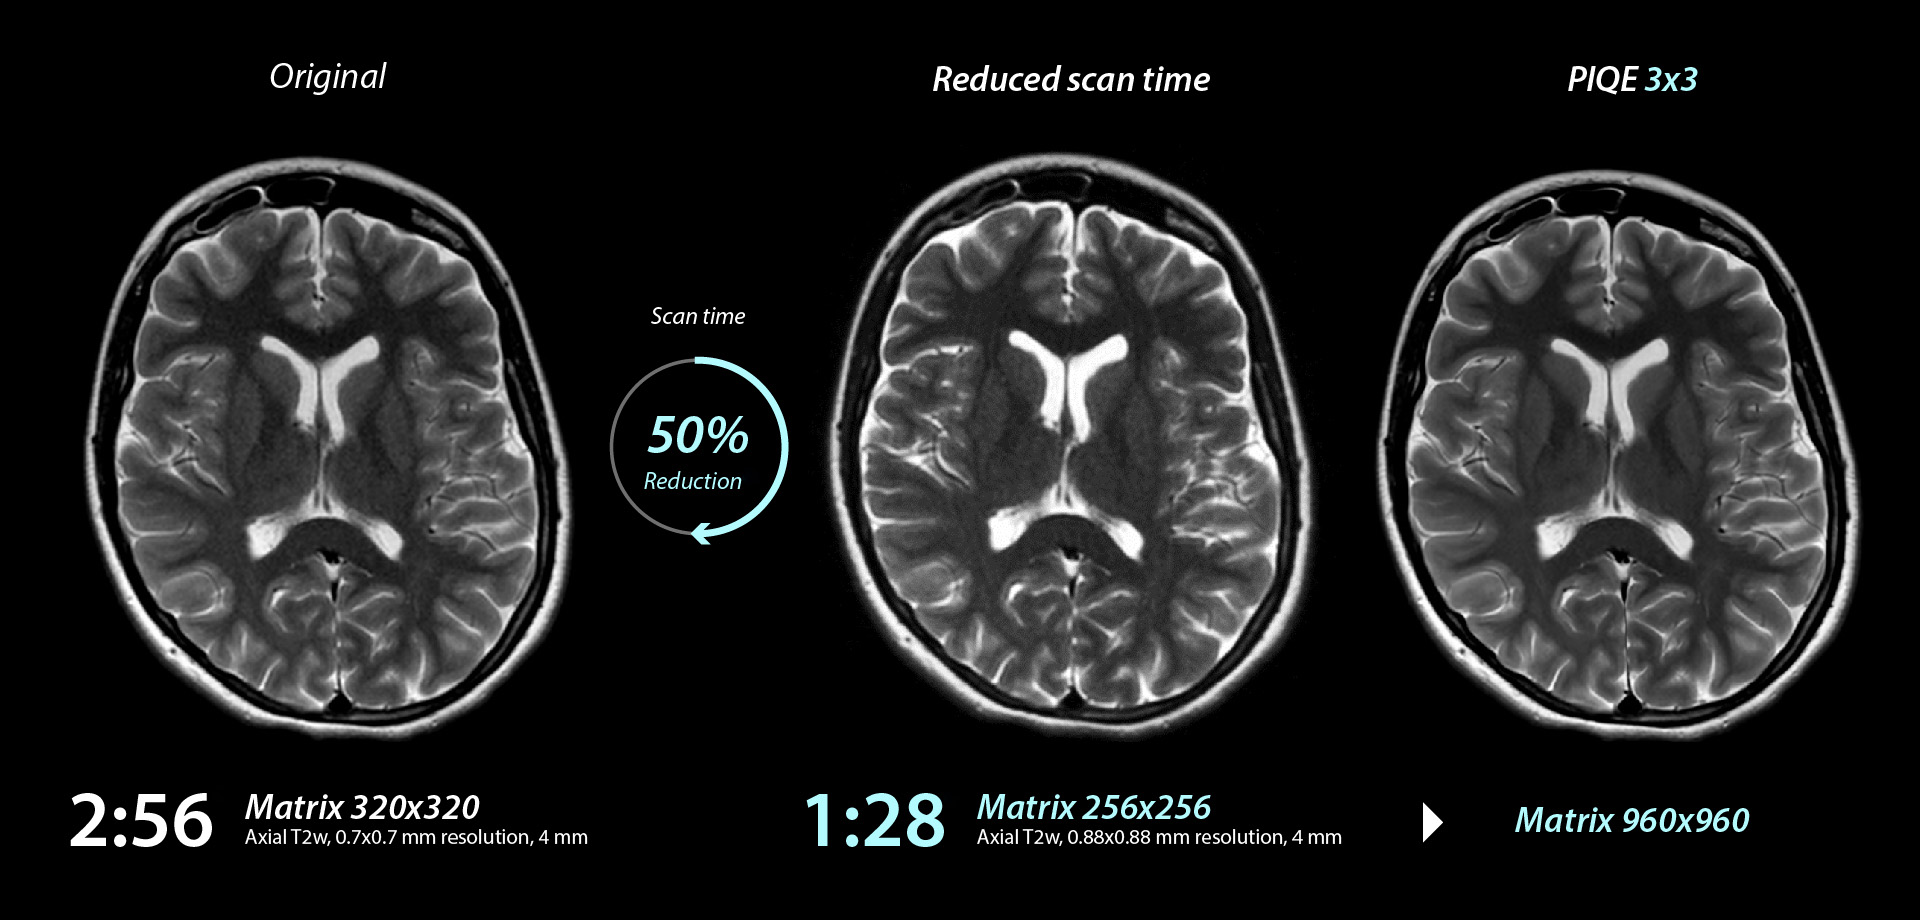

Brain

Vantage Galan 3T

Axi T2w for Brain

As this case is acquired with a 3T system, increasing the matrix over 512 × 512 will result in poor SNR and reduced contrast.

PIQE was applied after reducing the matrix to improve SNR and further shorten the scanning time.

As a result, scan time was reduced by 52% while still achieving high resolution.

Conventional

Axial T2w, Acquisition matrix 384 x 384, 0.58 x 0.58 mm resolution, 4 mm, 2:42

Conventional

Axial T2w, Acquisition matrix 320 x 320, 0.7 x 0.7 mm resolution, 4 mm, 1:18

PIQE

Axial T2w, Reconstruction matrix 960 x 960, 0.46 x 0.46 mm resolution, 4 mm, 1:18

Courtesy of Rothschild Foundation Hospital, France

Deep Learning Reconstruction for MR: PIQE

Precise IQ Engine (PIQE)

Accelerate high resolution imaging

PIQE accelerates scanning by reducing the acquisition matrix and enables acquisition of higher resolution images.

Actual scan time and scan time reductions shown throughout this gallery may vary by case.